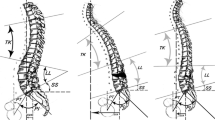

Three major metric parameters that account for a better result have been extensively validated: lumbar lordosis/pelvic incidence mismatch (LL–PI), pelvic tilt (PT) and sagittal vertical axis (SVA) [7, 8]. The first of these parameters (PI) is actually the only morphologic indicator of alignment and its advantage is that it can be measured independently of the patient’s position (i.e., in the surgical decubitus position); the other parameters are positional parameters that present themselves as the result of the interaction between spinopelvic morphology (PI–LL, and thoracic kyphosis—TK—mainly) and muscular activity, and can only be measured with the patient standing in a full lateral spine film [9]. Recent research has provided reliable methods to predict the positional parameters PT and SVA from patient’s age and morphological parameters (PI, LL, TK), thus permitting a calculation of the adequacy of alignment with the patient in decubitus. This finding is of paramount importance to intraoperatively predict the result of surgery in terms of alignment [10]. Different surgical maneuvers can be used to correct abnormal sagittal alignment. Minor amounts of PI–LL mismatch can be surgically addressed with standard surgical maneuvers (cage positioning, partial arthrectomy, posterior compression, rod contouring), and generally these maneuvers can increase the lumbar lordosis by 5°–7° per instrumented level. In some instances of collapsing spine (a major PI–LL mismatch is present and the spine is still flexible in traction or fulcrum-extension films), these methods can also provide correct alignment. Conversely [11], in non-flexible spines with a major LL–PI mismatch, greater corrections are needed and osteotomies of the spine are the most frequently used method of correction. Posterior column osteotomies [12, 13] have a more limited power of correction, in the range of 8°–10° per osteotomy level. The combination of large anterior cages with posterior column shortening osteotomies can provide a greater correction (10°–15° per level). Tricolumnar pedicle subtraction osteotomies (PSO) give a greater correction at a single point of the spine, ranging from 20° to 35° per level.

Lumbar PSO is indicated in the treatment of sagittal or sagittal and coronal deformity of the spine in presence of hypolordosis, spine stiffness (full correction cannot be achieved in fulcrum extension radiographs) and when the amount of necessary correction of LL is large (25° or more, Fig. 1). The decision to operate on an individual should take into account the severity of symptoms, the progression of the deformity and the clinical condition of the patient, as tricolumnar osteotomies of the spine carry substantial risk of complications. Also the expectations and functional needs of the patients should be considered and discussed, as the long fusions of the spine frequently needed for the correction of sagittal deformities in the lumbar spine determine a permanent functional limitation in patients. Whereas the elderly patients have the highest risk of complications associated to this surgery, they are the subgroup of patients who are more likely to obtain significant benefit from correction of the deformity, as has been shown by Smith et al. [15]. A complete surgical evaluation should include long-lateral standing films of the spine including the cervical spine and the hip joints in the same image and lateral fulcrum-hyperextension film in supine position, with the bolster at the level of the maximum deformity. From the standing full-spine film the necessary correction can be calculated based on geometrical methods [16, 17] (basically consisting in measuring the target angle of the osteotomy as a combination of the angular translation of C7 and the change in pelvic version required). Similarly, non-geometrical methods of calculation of the required correction can be used. These are based on the experimental verification for a given pelvic incidence, and a given combination of LL and TK, which causes a correct standing alignment [18]. If no other deformities are present (i.e., kyphosis in the thoracolumbar transition), the target lumbar lordosis can simply be calculated by adding 10° to the given PI in this specific patient [14]. A more exact non-geometrical calculation can be made based on the relationship between PI and LL experimentally found in asymptomatic volunteers [19]. Some of these methods lack a calculation of the potential increase in thoracic kyphosis after surgery (especially in patients with compensatory thoracic hypokyphosis in whom the thoracic spine is not included in the fusion area) and the surgeon should take the TK change into account, as it could result in final hypocorrection of SVA/PT. When correctly used, both geometrical and non-geometrical methods of calculation of the necessary correction can provide satisfactory results (Table 1).

The choice of level for the osteotomy depends on several factors. When a sagittal angular deformity is present, the osteotomy should ideally be performed at the apex of the sagittal deformity. Another relevant factor is the convenience of restoring the normal shape of the spine, where 60 % of the lordosis is located between L4 and S1. Most patients have the largest lack of lordosis in the lower lumbar spine, and for this reason the authors most frequently perform the PSO at L4. This permits having three levels of fixation below (L5, S1 and the ilium) (Fig. 2). An additional reason to perform the osteotomy at L4 (unless the most relevant deformity is in the upper lumbar spine) is that a PSO at a more caudal level provides better correction of the PT while maintaining good potential of correction of the SVA [20]. In the authors’ experience, PSOs at L3 or higher frequently result in good correction of SVA with persisting increased PT, suggesting that the need for active compensation (which leads to persistence of symptoms) has not been completely been solved.